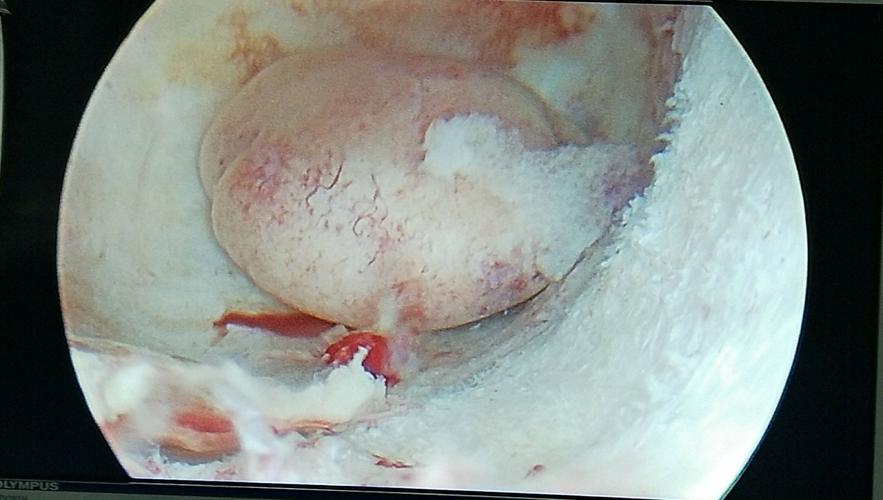

宫腔镜正常子宫图片

宫腔镜正常子宫图片,宫腔镜疼吗

重度宫腔粘连图片

宫腔粘连什么样的图片

宫腔息肉的照片